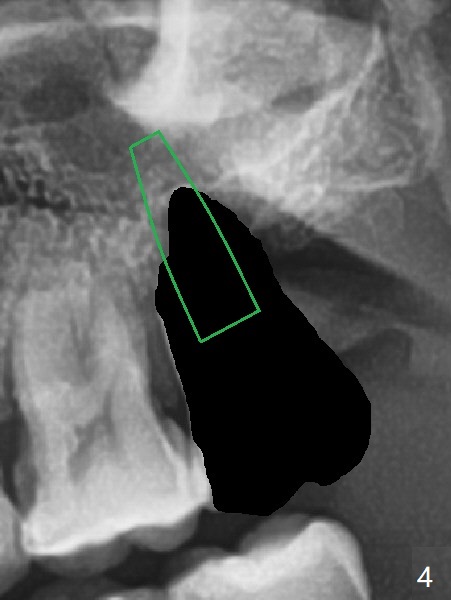

步骤一:选择大小长度合适植体(图四:绿色)。尽量大卡在近中,远中骨壁,取得初步稳定性,但是留下足够颊侧,腭侧空间植骨。植体上缘刚刚越过窦底,下缘龈下3-4毫米。